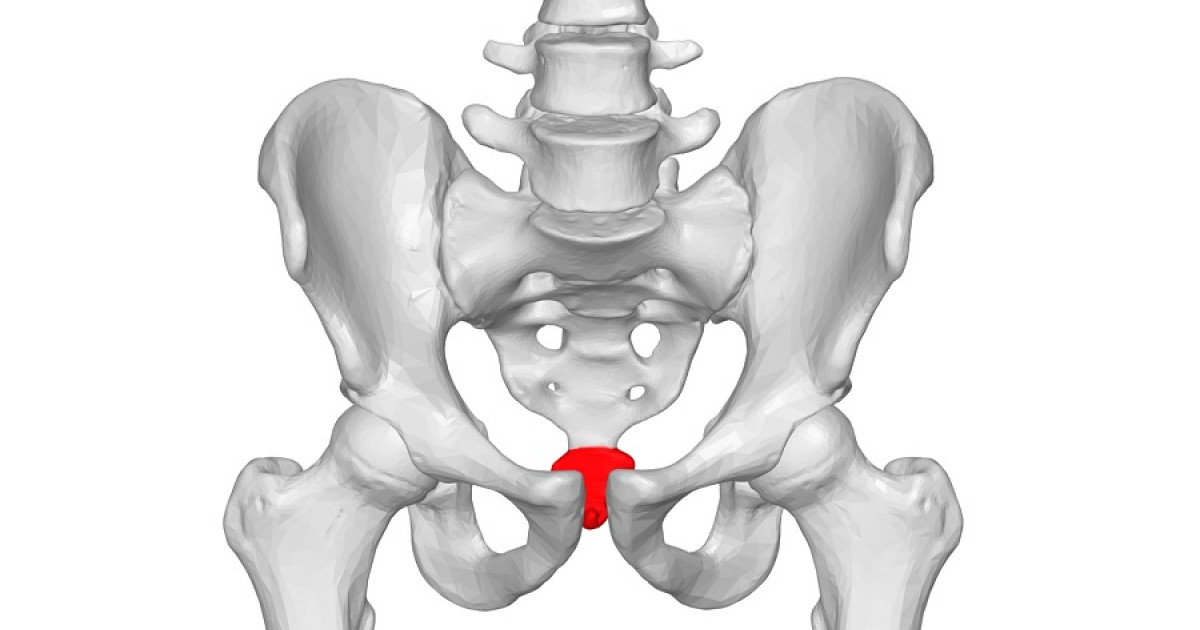

Структура позвоночника: сегменты и тазовые отделы в фотографиях